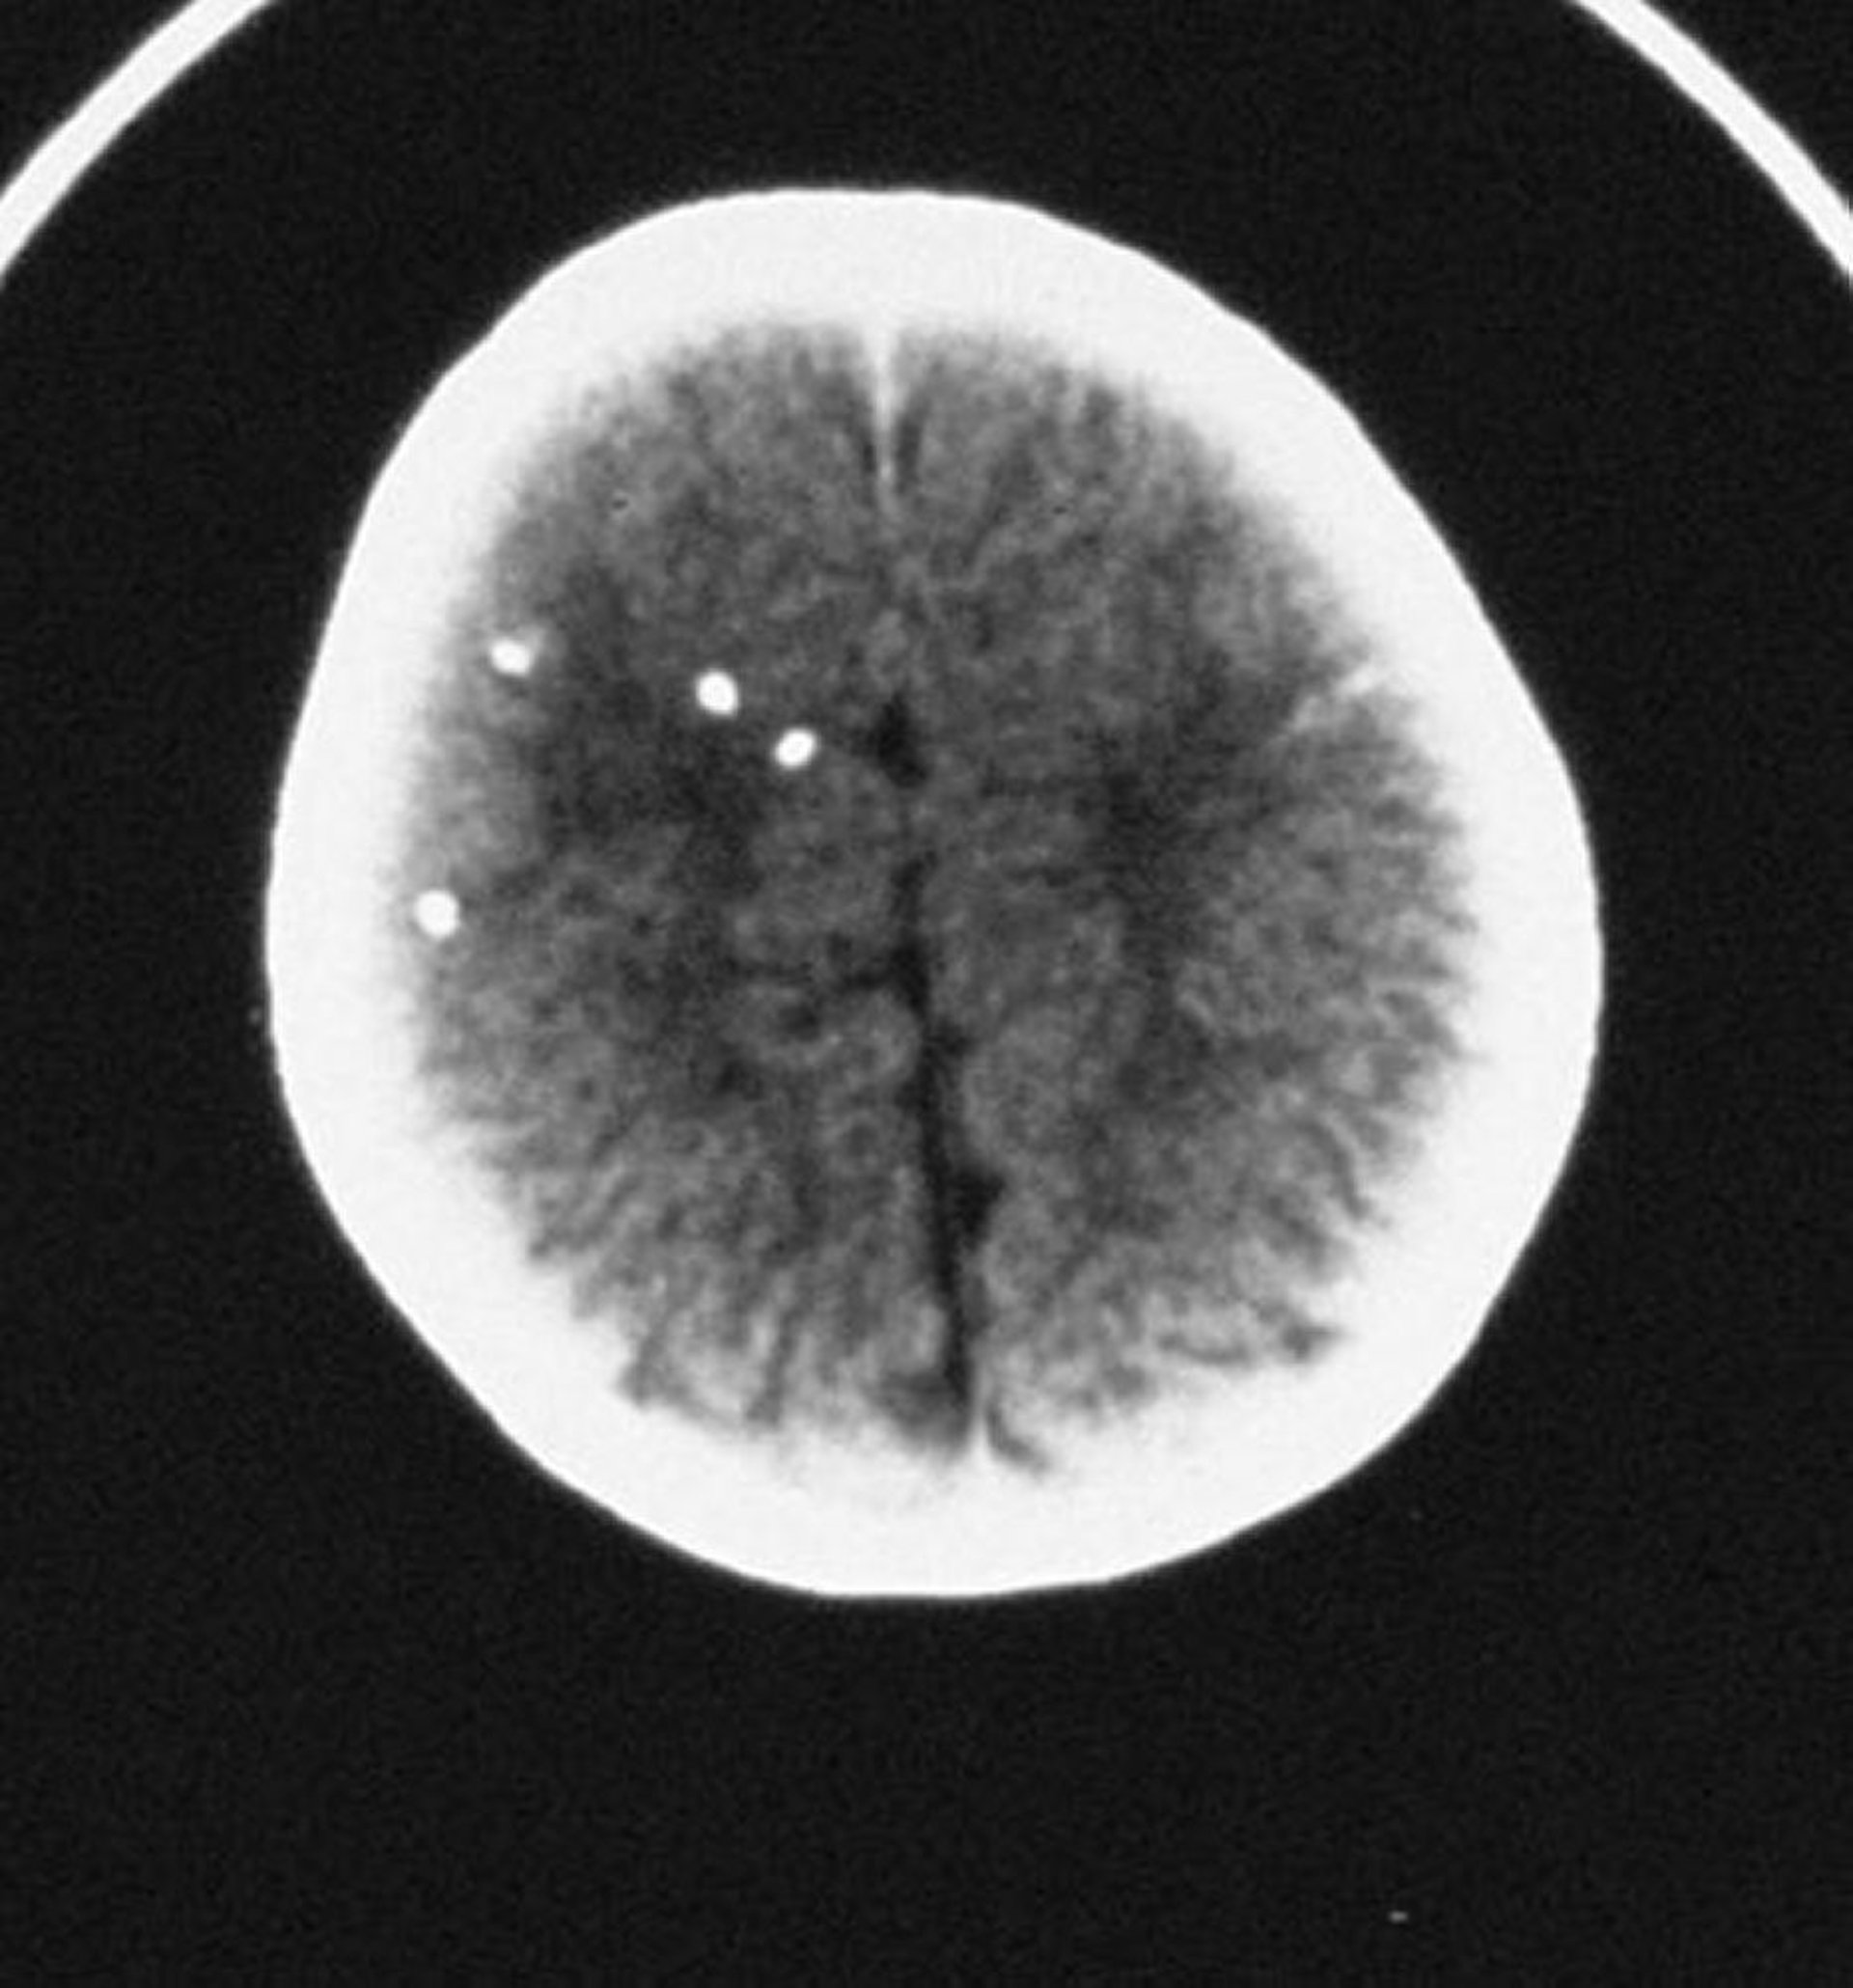

Toxoplasmose congénitale

Cette TDM montre des calcifications intracrâniennes éparses.